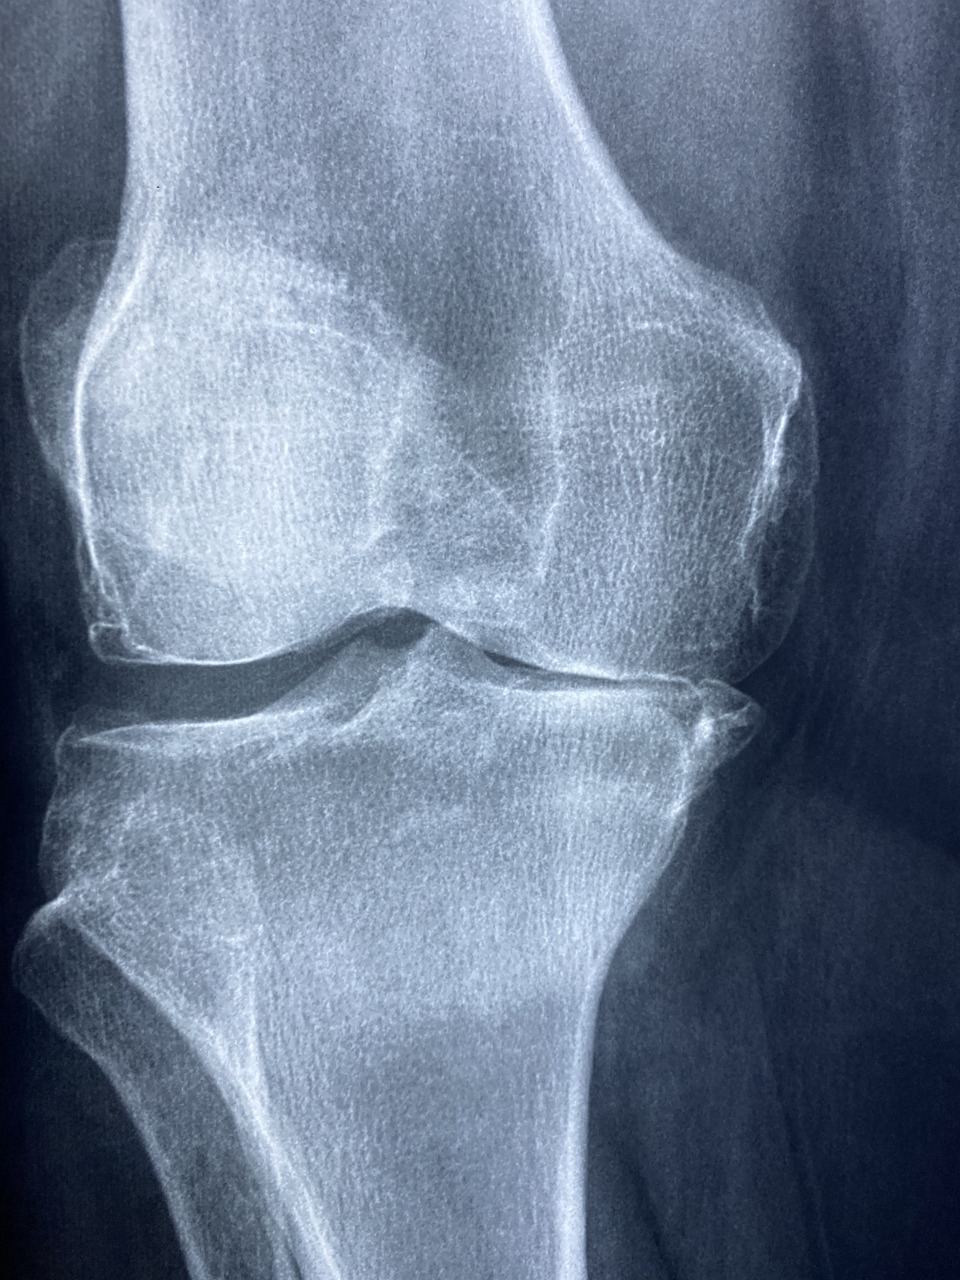

- ✔ 무릎 인공관절 수술비 지원

📌 무릎 인공관절 수술비 지원

- ✔ 한쪽 무릎: 최대 120만 원 지원

- ✔ 양쪽 무릎: 최대 240만 원 지원